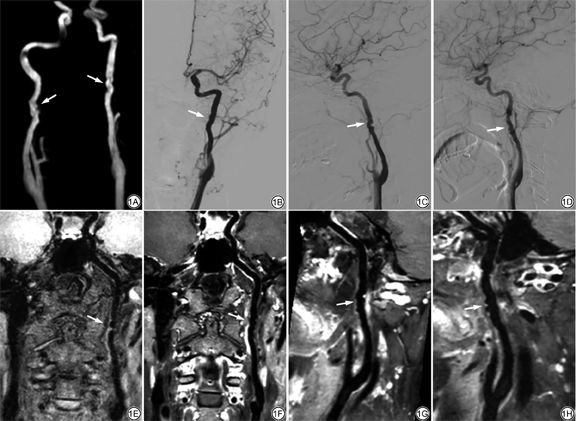

女,39岁,双侧颈内动脉多灶性肌纤维发育不良。A:MRA重建图示双侧颈内动脉C1段串珠样改变(白箭);B~D均为DSA图,B为左侧颈内动脉正位片,C为左侧颈内动脉侧位片,D为右侧颈内动脉侧位片,白箭处可见病变血管呈串珠状改变;E、F分别为T1WI增强前、后的冠状位曲面重建图,左侧颈内动脉病变位于颈1~2椎体水平,增强后明显强化(白箭);G、H分别为左侧颈内动脉、右侧颈内动脉T1WI增强后的矢状位曲面重建图,病变管腔形态改变分别同C、D图,呈串珠状,管壁呈波浪状改变,厚薄欠均,伴明显强化

A 39-year-old woman with multifocal fibromuscular dysplasia involved bilateral internal carotid artery (ICA). A: MRA reconstructed image shows the C1 segment of right and left ICA have a “string-of beads” appearance (arrows). B-D: DSA images, B shows anteroposterior film of left ICA, C shows lateral film of left ICA, D shows lateral film of right ICA, the lesions show string-of beads appearance (arrows); E, F are coronal view of pre-contrast and post-contrast T1-weighted images by curved planar reformation, the left ICA has a typical string-of-beads appearance at the level of the first, second cervical vertebrae, the lesion exhibits intense enhancement (arrows). G, H are sagittal view of post-contrast T1-weighted images by curved planar reformation of left and right ICA, lumen morphology changes like “string-of beads”, which are the same with C and D, respectively, and the vessel walls show wavy change, heterogeneous thickness, with obvious enhancement (arrows).